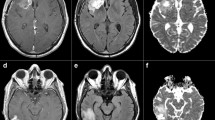

Diffusion-weighted images (DWIs) were acquired in twenty-three patients following surgery, prior chemoradiation and within 7 days following completion of treatment, using b-values ranging from 0 to 5000s/mm2. Mono-exponential diffusion (apparent diffusion coefficient: ADC), isotropic (non-directional) DKI model with apparent diffusivity (Dapp) and kurtosis (Kapp) estimates as well as SE model with distributed-diffusion coefficient (DDC) and mean intra-voxel heterogeneity (α) were computed for all patients prior and after chemoradiation. Median values were calculated for normal appearing white matter (NAWM) and contrast-enhancing tumor (CET). The magnitudes of diffusion change prior and after chemoradiation were used to predict overall survival (OS).

Diffusivity in NAWM was consistent for all diffusion measures during chemoradiation, while diffusivity measurements (ADC, Dapp and DDC) within CET changed significantly. A strong positive correlation existed between ADC, Dapp, and DDC measurements prior to chemoradiation; however, this association was weak following chemoradiation, suggesting a more complex microstructural environment after cytotoxic therapy. When combined with baseline tumor volume and MGMT status, age and ADC changes added significant prognostic values, whereas more complex diffusion models did not show significant value in predicting OS.

Despite increased tissue complexity following chemoradiation, advanced diffusion models have longer acquisition times, provide largely comparable measures of diffusivity, and do not appear to provide additional prognostic value compared to mono-exponential ADC maps.